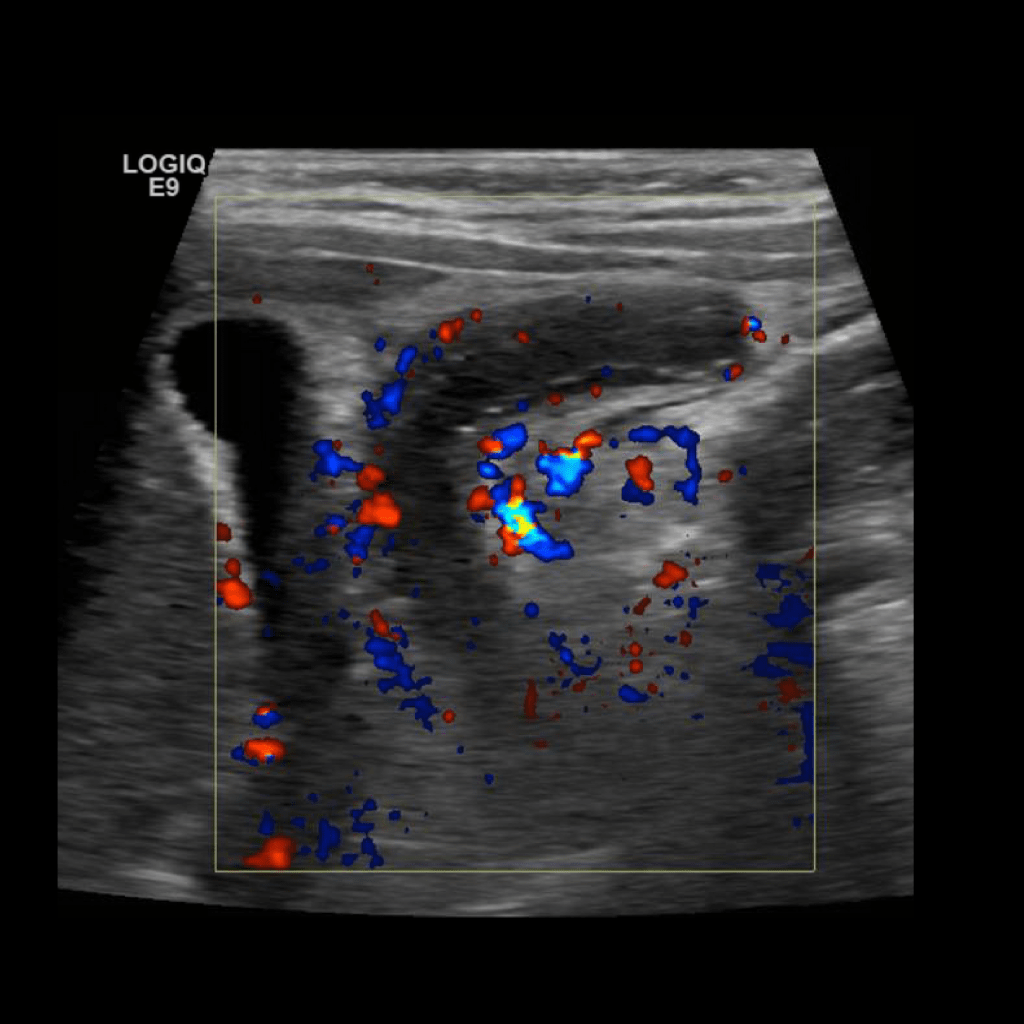

Appendicitis 14

Large appendicitis with appendicolith, hyperemia, fat standing and lympadenitis.